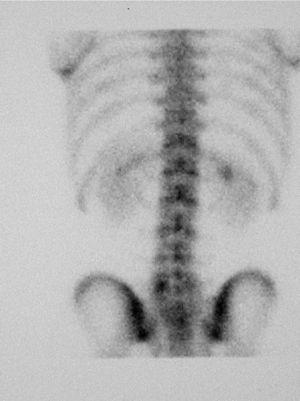

Als 15 dies el pacient es presenta amb simptomatologia atenuada. La GOP/SPECT (figs. 3 i 4) demostra fenòmens de remodelació òssia al nivell d'ambdues pars d'L5. Per tant, es conclou el diagnòstic d'espondilòlisi activa L5 dreta i espondilòlisi esquerra en formació. Es continua el mateix tractament i s'hi afegeix una pauta específica d'exercicis deslordosants i ortesis plantars de correcció.

Figura 3